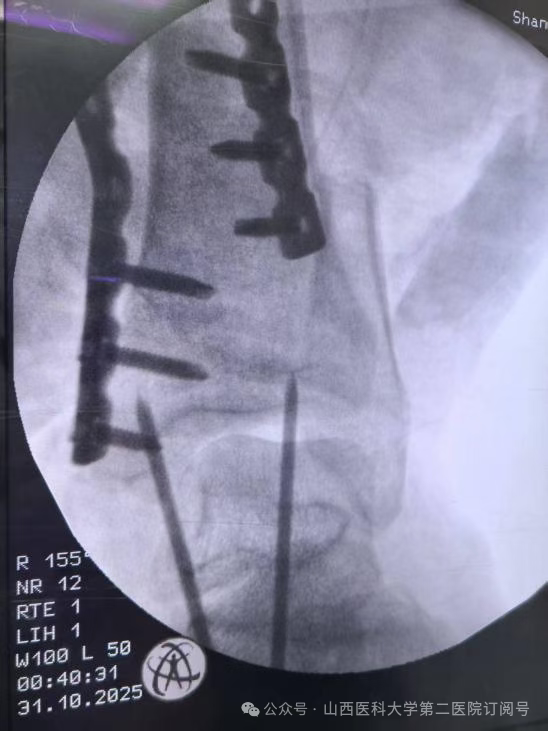

手术台上,每一步都至关重要。在总住院张桦栋医师、显微手外科董建峰主任、王怀刚医师的带领下,手术团队展现了高超的骨显微外科技术。精确地分离、保护重要的神经和血管,确保移植肢体的血供;在毫米之间进行骨骼的截除与重塑;将肌肉、肌腱等软组织进行精确对位缝合,以重建动力系统。整个手术过程犹如在显微镜下雕琢一件生命艺术品。麻醉科张林忠主任、贺萱医师主持麻醉,手术室田小荣护士长,霍元玲、刘萍护师熟练配合历时六小时,最终圆满成功,患者股动脉的血液源源不断地重新滋养左足。术后,患者生命体征平稳,移植的足部血运良好。

骨科总住院医师张桦栋医师介绍:“这个手术的理念堪称重塑。其核心原理是将受损严重的左小腿部分及左膝切除,保留功能完好的足部,并将其旋转180度后,与大腿股骨进行固定融合。这样一来,原本的踝关节就扮演起了膝关节的角色。形象地说,这就像进行了一次精密的“人体拼装”:将脚踝调转方向,与大腿连接。术后,通过专业的康复训练,患者可以利用这个“新的膝关节”(即原来的踝关节)进行屈伸活动,从而驱动假肢,实现更自然、更有力的行走。这远比传统大腿截肢后佩戴的假肢功能更优,能量消耗更少,步态也更接近正常人。